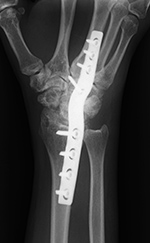

Plates

are most commonly used for fixation of long

bones, but they also are used in the spine and for

arthrodesis of the wrist (figure: wrist arthrodesis) (Ruedi, 2007; Benjamin, 1994). When diaphyseal fractures in the long

A newer design of DCPs is the low-contact

DCP (LCD), which reduces the area of contact “footprint” between the plate and bone. This design

produces less compromise to the capillary

network of the periosteum, which leads to a relative

improvement in cortical perfusion (figure: wrist arthrodesis with LCD).

The distribution of the holes and even stiffness of

this plate allow gentle and elastic deformation of

the entire plate without stress concentration at

one of the screw holes, as occurs with the standard DCP.

The footprint of the low-contact DCP has a trapezoidal

shape, and the screws can be inserted in

the plate in different modes: compression, neutral,

and buttress (Ruedi, 2007; Benjamin, 1994; Berquist, 1995; Freiberg, 2001; Hunter, 2001).

| Wrist arthrodesis with low contact dynamic compression plate |